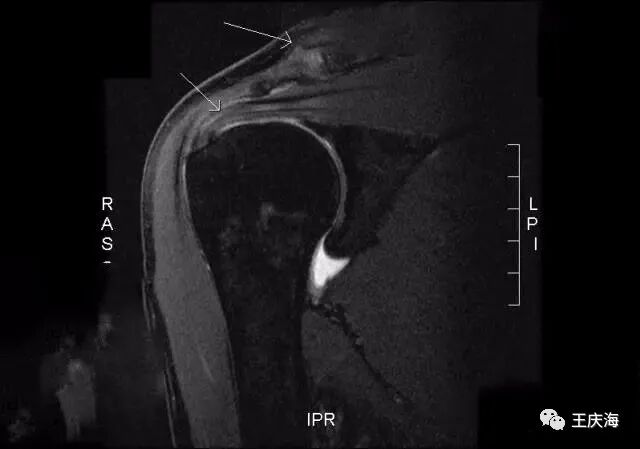

(3)MR:主要对肩袖、二头肌腱、盂唇、滑膜、软骨和肩峰下滑囊等结构进行检查。

依据核磁及关节镜下表现进行分期:

Ⅰ期MR检查未见异常,镜下见肩袖上表面毛糙,喙肩韧带表面有磨损表现;

Ⅱ期肩袖肌腱上表面部分撕裂,喙肩韧带和肩峰下表面有撞击磨损表现;

Ⅲ期肩袖出现全层撕裂,肩峰形状为二型或三型。